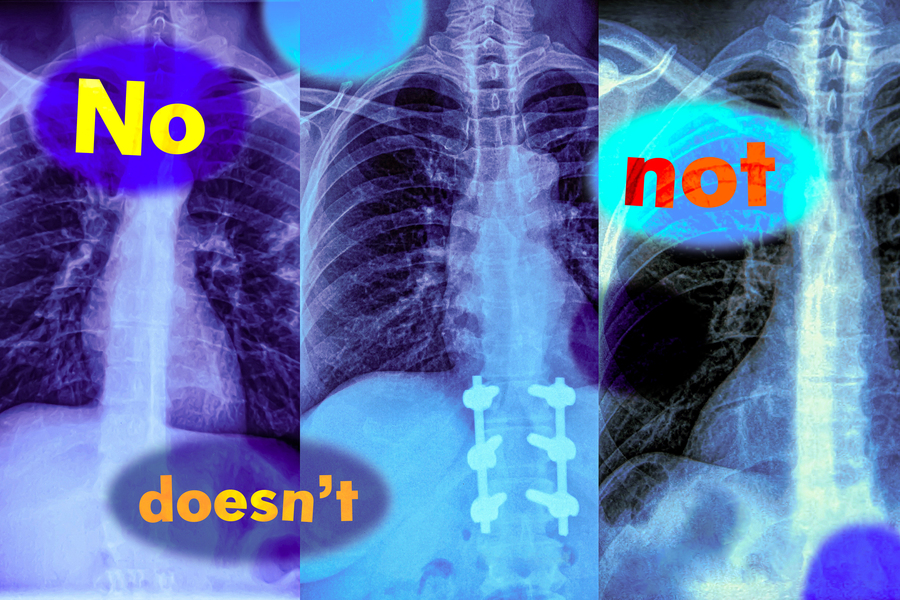

MIT researchers found that vision-language models, which are widely used to analyze medical images to streamline diagnosis, do not understand negation words like “no” and “not” (Credits: iStock; MIT News).

In a new study, MIT researchers have found that vision-language models are extremely likely to make such a mistake in real-world situations because they don’t understand negation — words like “no” and “doesn’t” that specify what is false or absent.

“Those negation words can have a very significant impact, and if we are just using these models blindly, we may run into catastrophic consequences,” says Kumail Alhamoud, an MIT graduate student and lead author of this study.